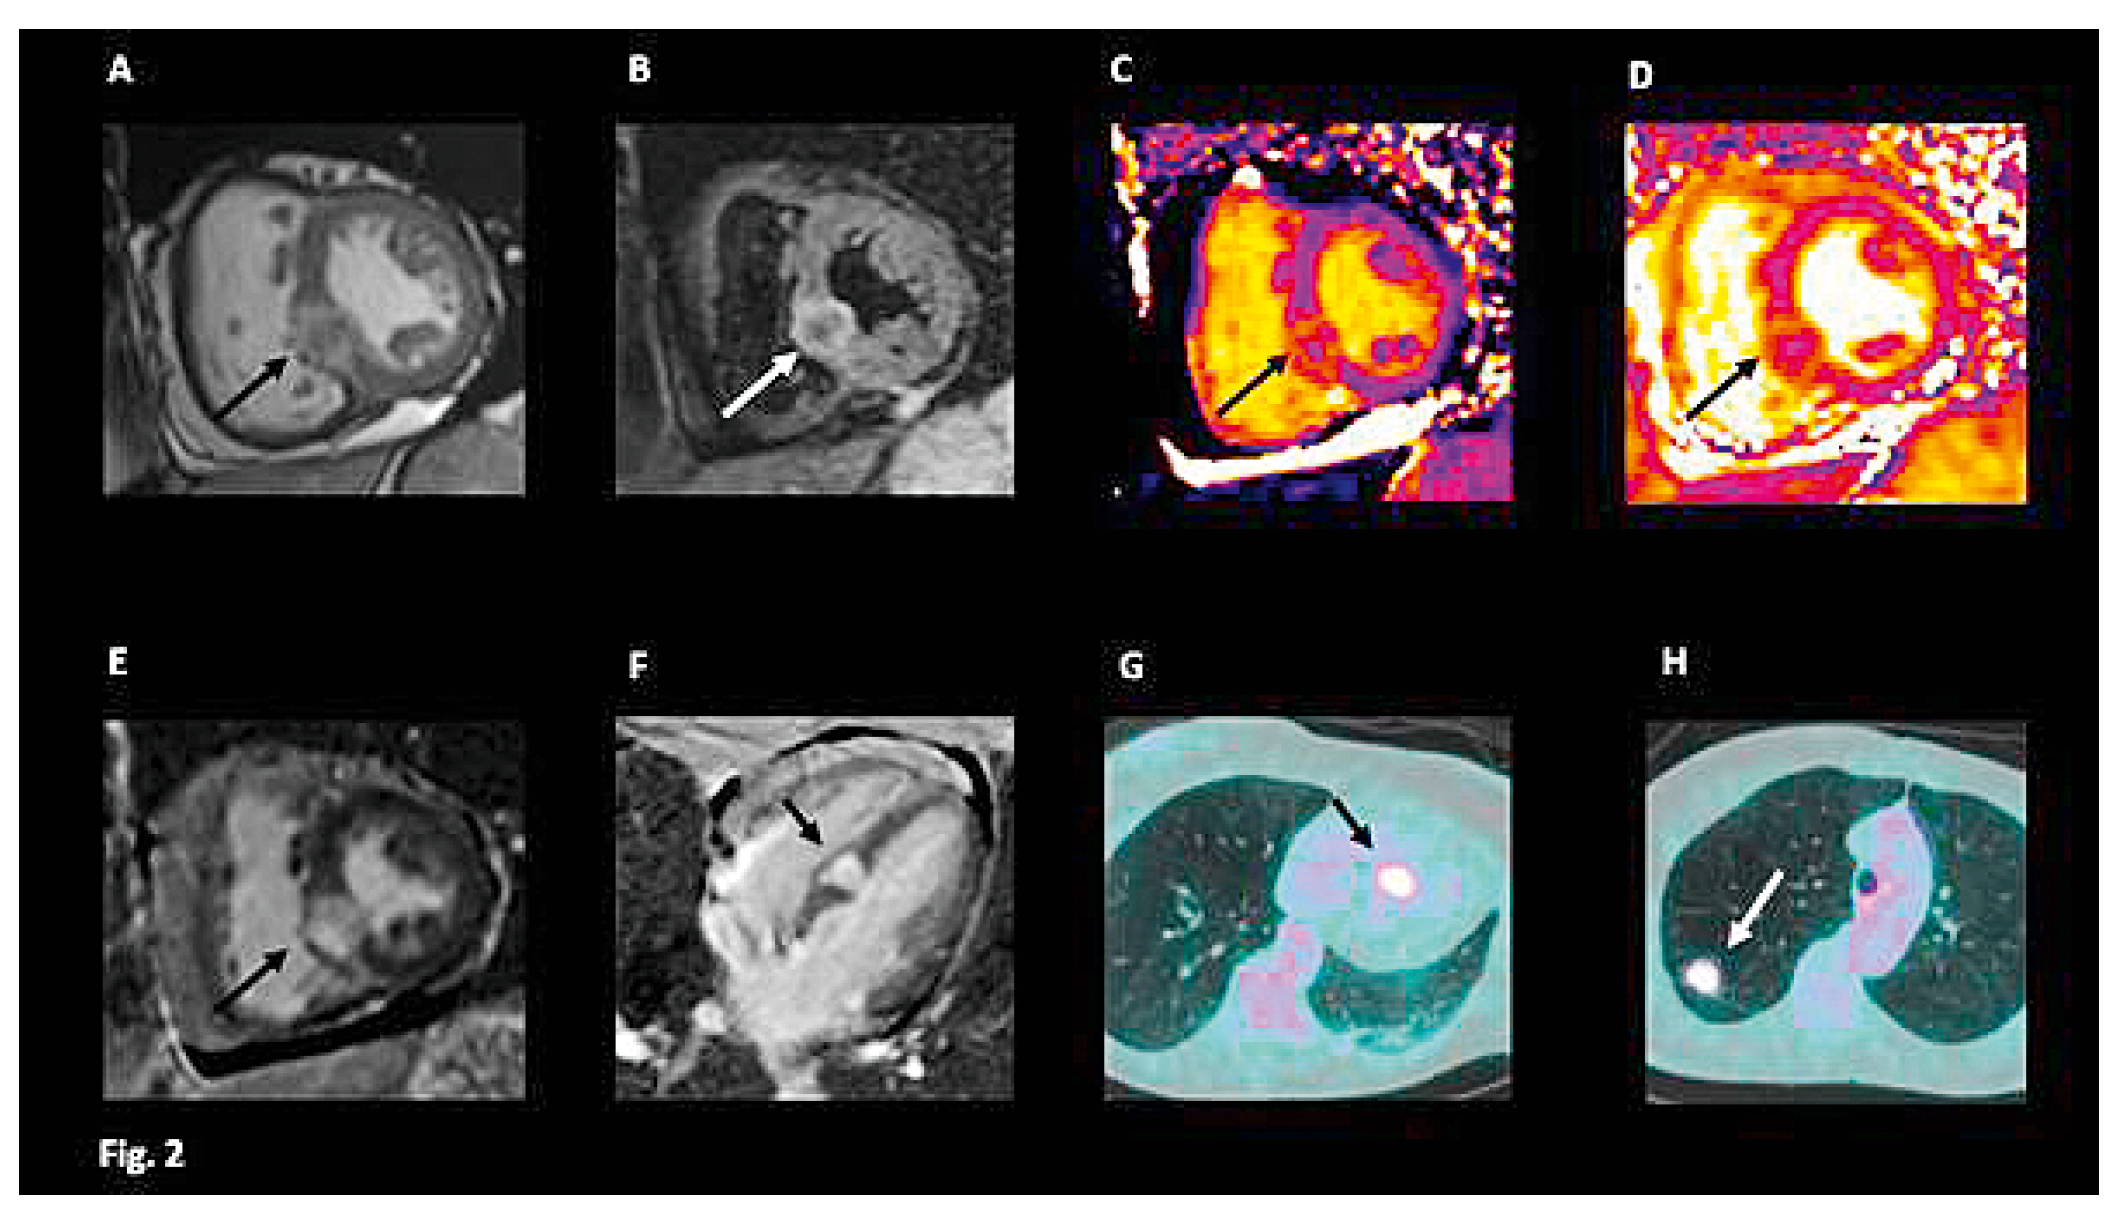

O14—Cardiac metastasis of a lung adenocarcinoma manifesting as an electrical storm

A 66-year old female was hospitalized in our Cardiovascular Department for a first episode of syncope. Clinical history revealed smoking and hypercholesterolemia. The baseline ECG showed repetitive non-sustained ventricular tachycardia (VT) of rather narrow QRS duration originating from the infero-basal interventricular septum (IVS) or from the right moderator band (Figure 1). A coronary angiography revealed a 50–70% stenosis of the left main coronary artery treated with the implantation of an active stent.The echocardiography was non-contributive, but the cardiac MRI revealed a localized thickening of the inferior IVS (Figure 2A) with hyperintense inhomogeneous appearance on T2-weighted images (Figure 2B) confirmed by elevated T2 values (60 ms, normal values <55 ms; Figure 2D) and T1 values (1184 ms, normal values <1050 ms; Figure 2C); the high signal intensity on late gadolinium enhancement (LGE, Figure 2E-2F) was indicative of a large interstitial space secondary to edema (high T2 and T1 values) and hypervascularization. The following differential diagnoses were considered: cardiac sarcoidosis, metastatic tumor or infectious disease. Endomyocardial biopsy samples taken from the IVS did not show any malignant cells or granuloma. An electrophysiological study did not show any susceptibility to sustained ventricular arrhythmias. The unexplained 8-Kg weight lost over the past year in a smoker patient raised the suspicion of malignancy. An 18FDG-PET scan performed after a 24-hour carbon hydrate free diet revealed a focal hypermetabolic activity within the IVS at the site of LGE (Figure 2G). Interestingly, a hypermetabolic nodule in the upper lobe of the right lung (Figure 2H) together with active paratracheal lymph nodes were suggestive of a metastatic lung cancer, that was confirmed by cytoponction of paratracheal lymph nodes (non-small cell lung cancer: NSCLC). The patient started a combination chemotherapy with carboplatin and pemetrexed and now is followed by the oncologists and the cardiologists.

Conclusions: this clinical case represents an unusual manifestation of lung cancer (NSCLC) with cardiac metastasis presenting with repetitive non-sustained ventricular tachycardia. In this patient, cardiac MRI allowed to detect the cardiac metastasis and was useful to guide the endomyocardial biopsy and the elettrophysiological study.

![]() |

| Figure 1. ECG. |

| Figure 2. CMR. |